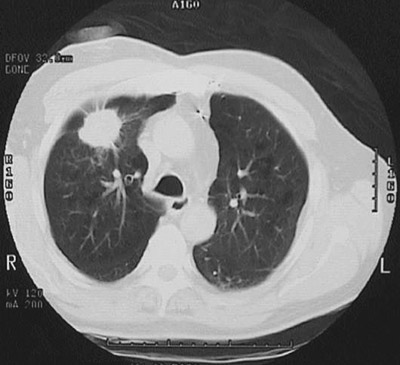

This chest CT scan at "lung window" density reveals a bright mass that on fine needle aspiration biopsy was found to be an adenocarcinoma.